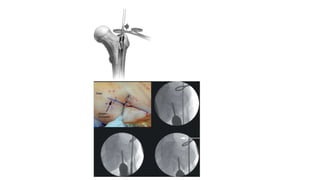

•Error:

•El rimado proximal

dirigido demasiado

medial conducirá a un

varo (acentuado si hay

conminución medial)

•Rimar fragmento no

reducido

Rimado

Core Curriculum V5